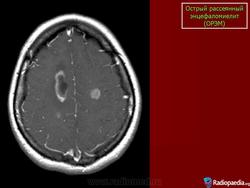

Основу патоморфологического процесса составляют периваскулярные множественные очаги демиелинизации с участием микроглии. Локализация процесса различна: белое вещество больших полушарий мозга, ствол мозга, спинной мозг. Периаксиальный демиелинизирующий процесс обнаруживается и в спинномозговых корешках и нервах конечностей.

Диагностика. Диагноз основывается на остром инфекционном начале, наличии симптомов мультифокального полисистемного поражения. Дифференцировать рассеянный энцефаломиелит следует от энцефаломиелитов при кори, ветряной оспе, краснухе. Основное значение при этом имеют данные анамнеза. Более сложен дифференциальный диагноз с рассеянным склерозом. В большинстве случаев окончательный диагноз устанавливается после длительного наблюдения. Наличие рецидивов и ремиссий свидетельствует о рассеянном склерозе.